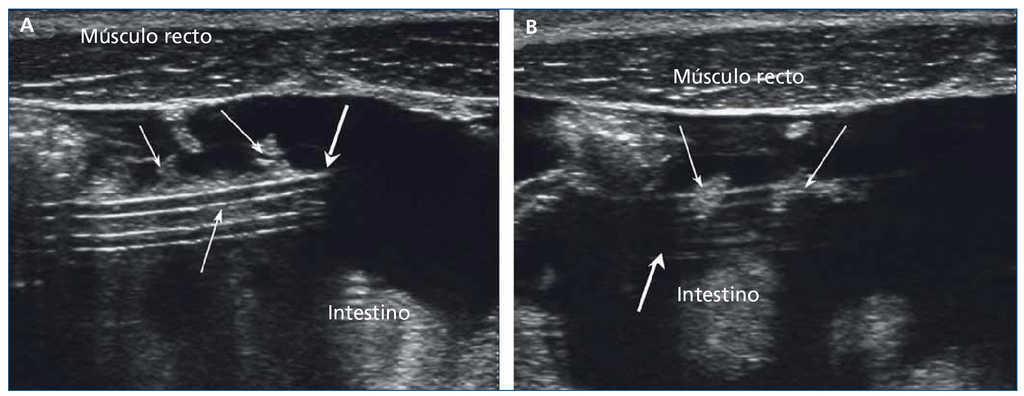

El éxito de la DP depende del correcto funcionamiento del catéter implantado5. El atrapamiento por epiplon (figura 2) es una causa frecuente de obstrucción del catéter peritoneal6. La incidencia de baja ultrafiltración por obstrucción del catéter varía, según las series, entre un 6 % y un 20,5 %, siendo entre el 52 % y el 92 % atribuible a un atrapamiento peritoneal6. La cateteriografía7 ha sido propuesta para su diagnóstico, pero necesita un medio de contraste en la cavidad peritoneal, mientras que la ecografía es igual de eficaz, menos invasiva y permite cuantificar el grado de atrapamiento para diferenciar a aquellos pacientes que requerirán cirugía o maniobras de recolocación.

Figura 2.Atrapamiento peritoneal por epiplon. A) Epiplon (flechas finas) rodeando el catéter peritoneal. B) Introducción de epiplon en los orificios laterales del catéter peritoneal (flechas finas).